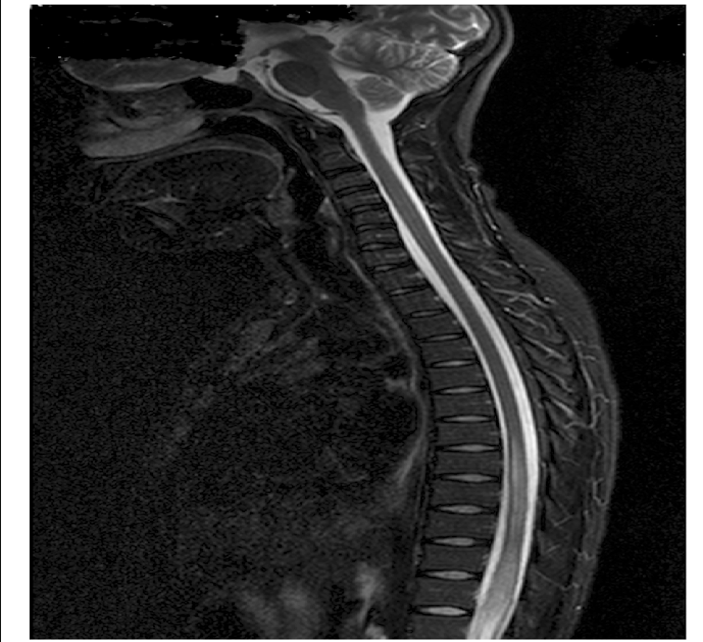

• Lesion extends over more than 3 vertebral segments.

• Central gray matter involvement.

• No cord compression.

• Bright T2 signal.

• Suggestive of NMO spectrum disorder.